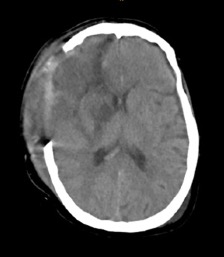

Ante la buena evolución, se decidió el traslado a una sala general. A las 24 h, el cuadro se complicó con un episodio súbito de depresión del sensorio, con un puntaje de la escala de Glasgow 8/15, pupilas mióticas e hiporreactivas. Por tal motivo, se decidió realizar una nueva tomografía computarizada de cráneo que reveló un hematoma intraparenquimatoso cerebral derecho (Figura 1). Volvió a ingresar en la Unidad de Cuidados Intensivos, recibió asistencia respiratoria mecánica y fue sometida a cirugía mediante una evacuación del hematoma intracerebral derecho, craniectomía descompresiva frontotemporal derecha y plástica dural (Figura 2). A los siete días del procedimiento quirúrgico, tuvo registros febriles, por lo cual se decidió realizar dos hemocultivos, retrohemocultivos, un aspirado traqueal y una punción lumbar, cuyo resultado fue: líquido cefalorraquídeo turbio con 10.000 elementos (80% polimorfonucleares, 20% monomorfonucleares), proteínas 0,6 g, glucosa 0,20 g y lactato 20 mmol/l. Se administró un tratamiento empírico con meropenem/vancomicina. A las 48 h, los resultados del estudio bacteriológico informaron Enterococcus faecalis en el cultivo de líquido cefalorraquídeo y hemocultivos X2 con la misma sensibilidad y resistencia. Se procedió a ajustar el tratamiento antibiótico según el antibiograma, por lo que se suspendió la combinación de meropenem/vancomicina y se administró ampicilina sulbactam/ceftriaxona. A las 72 h, la paciente sufre un paro cardiorrespiratorio y fallece.

Figura 2. Tomografía computarizada de cráneo

luego del drenaje del hematoma intraparenquimatoso.